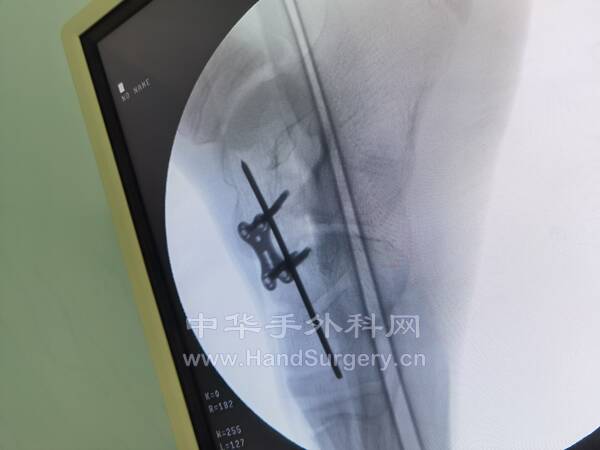

6.打外固定架顺序:

1.4.0mm全针自腓骨下段向腓骨侧贯穿固定,上一个半环,上棒夹2枚

2.5.0mm半针自胫骨背内侧垂直打入胫骨,与半环相连,上钉夹1枚

3.4.0mm全针自跟骨远端贯穿打入,两边各上支撑杆1枚及2枚钉夹与胫腓骨间的全针相连

4.3.5mm半针打入第五跖骨远端,另一个3.5mm半针打入第一跖骨远端,两端各上一个支撑杆和两枚棒夹与半环相连